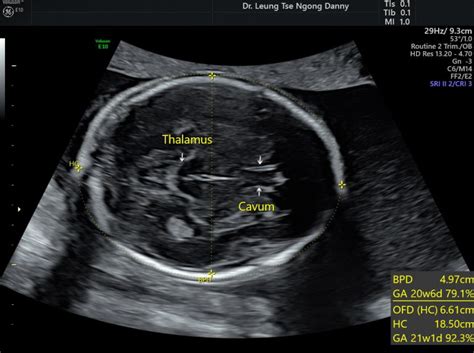

Head Circumference (HC) is a vital measurement in fetal biometry, providing insights into the baby’s brain growth. At 28 weeks, the normal range for HC typically falls between 25.3 cm and 28.3 cm. This measurement is obtained by carefully tracing the outline of the baby’s head on an ultrasound image. It’s important to remember that these are just average ranges, and slight variations can occur depending on individual factors. Factors influencing HC include genetics, maternal health, and overall fetal growth patterns. If the HC measurement falls outside the typical range, your healthcare provider will investigate further to determine if there’s any cause for concern. This might involve additional ultrasounds or other tests to assess the baby’s development more comprehensively. It’s crucial to maintain regular prenatal checkups so your doctor can monitor these measurements and address any potential issues promptly. Remember, early detection and intervention can make a big difference in ensuring a healthy outcome for your baby. So, keep those appointments and don’t hesitate to voice any concerns you might have. Your healthcare team is there to support you every step of the way. Keeping track of head circumference helps doctors monitor brain development. Significant deviations from the normal range can indicate potential problems, such as microcephaly (smaller than normal head size) or macrocephaly (larger than normal head size). Regular monitoring and appropriate interventions are crucial for addressing any concerns and ensuring the best possible outcome for the baby’s neurological development. So, head circumference measurement is an important tool for monitoring fetal health.